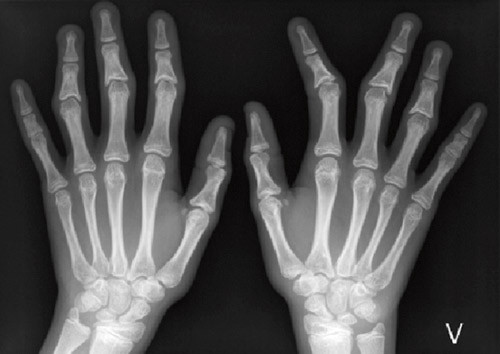

Grunnet mistanke om trikorhinofalangealt syndrom ble det tatt røntgenbilder av hendene, som viste korte falanger og kjegleformede epifyser. Røntgenundersøkelsene viste også forsinket skjelettmodning, svarende til 3,5 år. Pasientens høyde lå omtrent på 10-prosentilen, mens midtforeldrehøyden var i nærheten av 97,5-prosentilen. Kognitiv, sosial og øvrig utvikling var aldersadekvat.

En jente hadde fra 6 – 7-årsalderen fått langsomt økende skjevstillinger i flere fingerledd på begge hender. Senere ble det også påvist litt skjevt bitt. Røntgenundersøkelse før primærundersøkelsen viste kjegleformede epifyser i grunnfalangen på 1. finger bilateralt samt i midtfalangen på flere andre fingre.

Pasient 3 hadde tynt hår, kraftig nese med meget små nesevinger, antydning til retrognati, tynn overleppe, tynne øyebryn lateralt og deformerte fingre. Røntgen av hendene viste kjegleformede epifyser, spesielt proksimalt på midtfalangene. Hun hadde skjøre negler, liten plass til tennene, som var skjeve, men i normalt antall.

Pasient 4 hadde også tynt hår, et stort neseparti med meget små nesevinger og tynne øyebryn lateralt samt deformerte fingre (fig 2a), med kraftige ledd. Også her viste røntgen av hendene (fig 2b) kjegleformede epifyser. Hun hadde litt skjeve tenner i normalt antall samt skjøre negler.